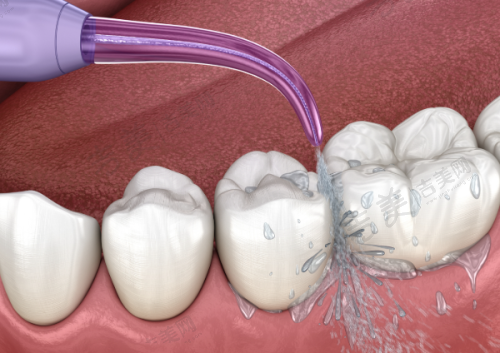

特色科室与项目:上海雅杰口腔诊所的科室设置和特色项目优势明显。科室方面,有口腔科、牙体牙髓病科、牙周病科等多个专精科室。特色项目包括种植牙、牙齿矫正、牙齿修复、儿童牙齿治疗等。种植牙项目采用数字化种植,拥有3D导板种植系统,可精细定位种植位置,减少创伤,修复更快。牙齿矫正中的隐形矫正使用口内扫描仪,5分钟扫描取模,不用咬恶心的石膏,还能即时出3D矫正方案。牙周治疗采用超声波洁牙机 + 激光治疗仪,洁牙更干净,激光消炎减少出血,不适感轻。儿童补牙配备疼痛较小局麻仪 + 卡通牙钻,缓慢给药减少疼痛,卡通造型缓解孩子紧张。这些特色项目凭借精良的设备和专精的技术,为患者提供了优质的口腔治疗体验。

合理亲民的价格:上海雅杰口腔诊所收费合理,价格亲民。常见项目价格如下:超声波洁牙168元起,儿童乳牙拔除29.9元起,窝沟封闭308元起,上颌正位智齿拔除780元起,冷光牙齿美白1180元起,全瓷牙冠1980元起,爱尔创全瓷牙2980元起,德国威兰德全瓷牙4980元起,瓷贴面美白2900元起,成人树脂补牙299元起,时代天使隐形矫正16800元起,国产传统金属托槽矫正8999元起,儿童早期干预矫正32000元起,瑞士士卓曼iti标准版种植牙8999元起/颗,德国贝格种植牙6999元起/颗,韩国dio种植牙2680元起/颗,美国皓圣种植牙4588元起/颗。老年人种牙价格方面,all - on - 4种植牙4593元起,种植牙纯钛桥架5463元起等。此外,该诊所在暑期还有优惠,如韩国种植体一颗特价3999元起,品牌二氧化锆全瓷牙2980元/颗起,传统金属托槽矫正特价9800元起,日式PMTC八步高端舒适洁牙980元起 。